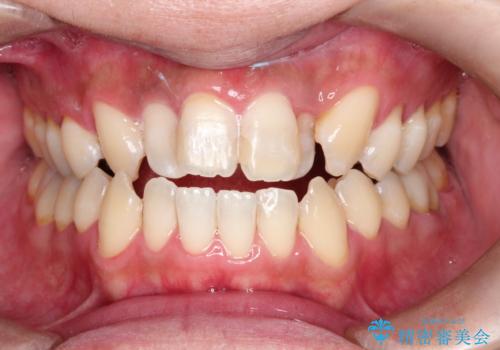

- すき間の部分の歯磨きがしずらく、クリーニング希望で来院されました。今後はセラミックによる治療を考えてとの事でした。PMTC(保険外治療)30分コースを行いました。

PMTC(保険外治療)とは、歯垢・歯石・着色などを除去することです。磨きのこしなどにより歯垢が付着し続けると、歯石に変化していきます。歯石になってしまったら、歯ブラシだけで落とすことができなくなります。そのため歯科医院での専門的な機械・材料を使用してのクリーニングが必要です。